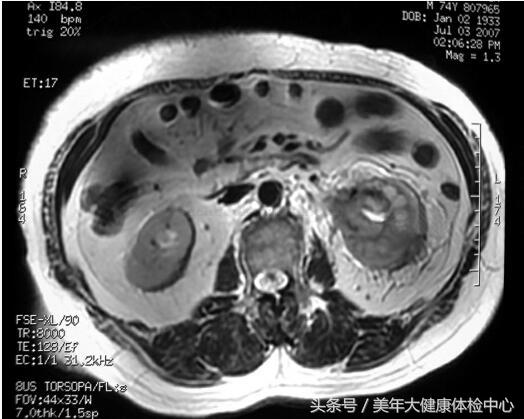

MR(图13-2):左肾盂、肾盏及肾周间隙病变,范围约4.5cm×3.5cm,形态不规则,边界不清,病变T1为等信号,T2低-等信号。动脉期有强化,实质期及延迟期增强更明显,肾周脂肪间隙见条索状强化。

图13-2 MR

肾集合管癌的影像学特点为:B超显示肾髓质内低回声信号肿物。由于集合管癌为少血供肿瘤,起源于肾髓质而常累及肾皮质、肾盂和肾盏,CT的主要特点为平扫可见累及肾髓质及肾窦的软组织肿块,病变呈浸润式生长,密度多均匀,形态不规则,边缘不清,动态增强为中度局限性延迟强化。MR的特点为肿瘤呈浸润式生长、边缘不清,T1为低-中等信号,T2为低信号,动脉期有强化,实质期及延迟期增强更明显。